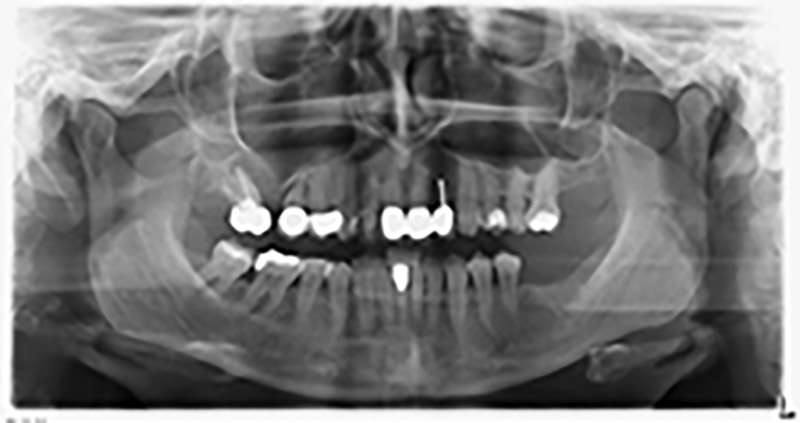

Etwa sechs Monate nach Extraktion der Zähne 16 und 14 wurde zur Planung und Risikominimierung eine digitale Volumentomografie (DVT, Planmeca) erstellt. Hierbei wurde deutlich, dass der Knochen sich nicht in der gewünschten Quantität regeneriert hat (Abb. 2 bis 7).

Um eine festsitzende Versorgung auf mindestens zwei Implantaten zu gewährleisten, ist eine Sinusbodenelevation sowohl in Regio 16 als auch in Regio 14 erforderlich. Da in diesem Fall das Restknochenangebot extrem gering ist, müsste ein verhältnismäßig großer Knochenaufbau durchgeführt werden. Große Knochenaufbauverfahren sind invasiv, mit einer höheren Patientenmorbidität verbunden, zeitintensiv und kostspielig. Die Vorhersagbarkeit der Behandlungsresultate ist geringer und das Misserfolgsrisiko höher. Vor dem Hintergrund dieser Nachteile, wurde die Patientin über eine herausnehmbare Alternative aufgeklärt, die sie jedoch konsequent ablehnte.

Um die Augmentation auf Regio 14 einzuschränken, wurde in Absprache mit der Patientin eine Schrägstellung des Implantats 16 nach dorso-kranial geplant (Abb. 8).